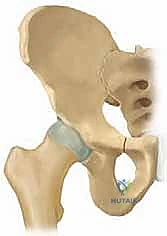

جراحة قطع عظم الحوض الثلاثي (TIO) هي إجراء جراحي يعيد توجيه التجويف الحقي لتحسين تغطية رأس الفخذ وعلاج خلل تنسج الورك، خاصة في الأطفال والمراهقين. يتم من خلال قطع عظام الحوض الثلاثة (الحرقفة، الإسك، العانة) لتمكين دوران التجويف الحقي حول رأس الفخذ، مما يزيد من استقراره ويقلل من خطر التهاب المفاصل المبكر.

من خلال إجراء قطوع دقيقة في عظام الحوض الثلاثة (الحرقفة، الإسك، العانة)، يتم تحرير التجويف الحقي بالكامل ليتم تدويره حول رأس الفخذ، مما يضمن استقراراً ميكانيكياً حيوياً للمفصل، ويمنع الخلع المتكرر، ويقي المريض من خطر الإصابة بالفصال العظمي (التهاب المفاصل التنكسي) المبكر الذي قد يستدعي زراعة مفصل صناعي في سن مبكرة.

لفهم أهمية جراحة (TIO)، يجب أولاً فهم التشريح المعقد لمفصل الورك. يُصنف مفصل الورك على أنه مفصل كروي حقي (Ball-and-Socket Joint). تتكون "الكرة" من رأس عظم الفخذ (Femoral Head)، بينما يتكون "التجويف" من الحق (Acetabulum) وهو جزء من عظم الحوض.

بمجرد اكتمال هذه القطوع الثلاثة، يصبح التجويف الحقي (الكوب) منفصلاً تماماً عن بقية الحوض، مع بقاء إمداداته الدموية سليمة.

4. إعادة التوجيه والتدوير (Rotation & Redirection)